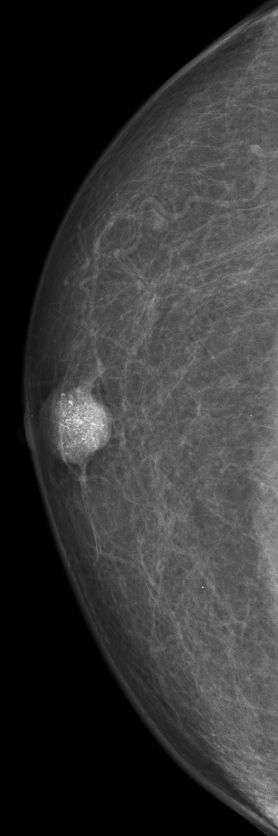

| DCIS | 80-jähriger Mann mit einem Knoten rechts retromamillär. Mammographie: Dichter Knoten mit multiplen Mikroverkalkungen unmittelbar periareolär. Histologie: papilläres DCIS, G2, 19 mm, ER: 12/12, PR: 6/12, Ki-67: 20%. Th.: Exzision, Radiatio der Mamma, TAM über 5 Jahre | ||||

rechts CC![]() |